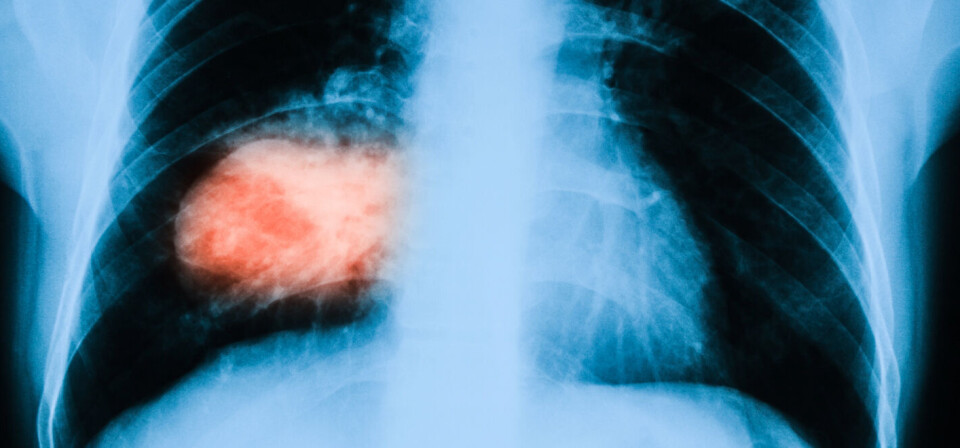

FDA gir ordinær godkjennelse til EGFR-hemmeren osimertinib, på bakgrunn av nye fase 3-data.

Kreftlegemiddelet osimertinib (Tagrisso) fra AstraZeneca har fått ordinær godkjennelse av den amerikanske legemiddelmyndigheten FDA. Legemiddelet er godkjent for å behandle EGFR-positiv ikke-småcellet lungekreft med spredning.